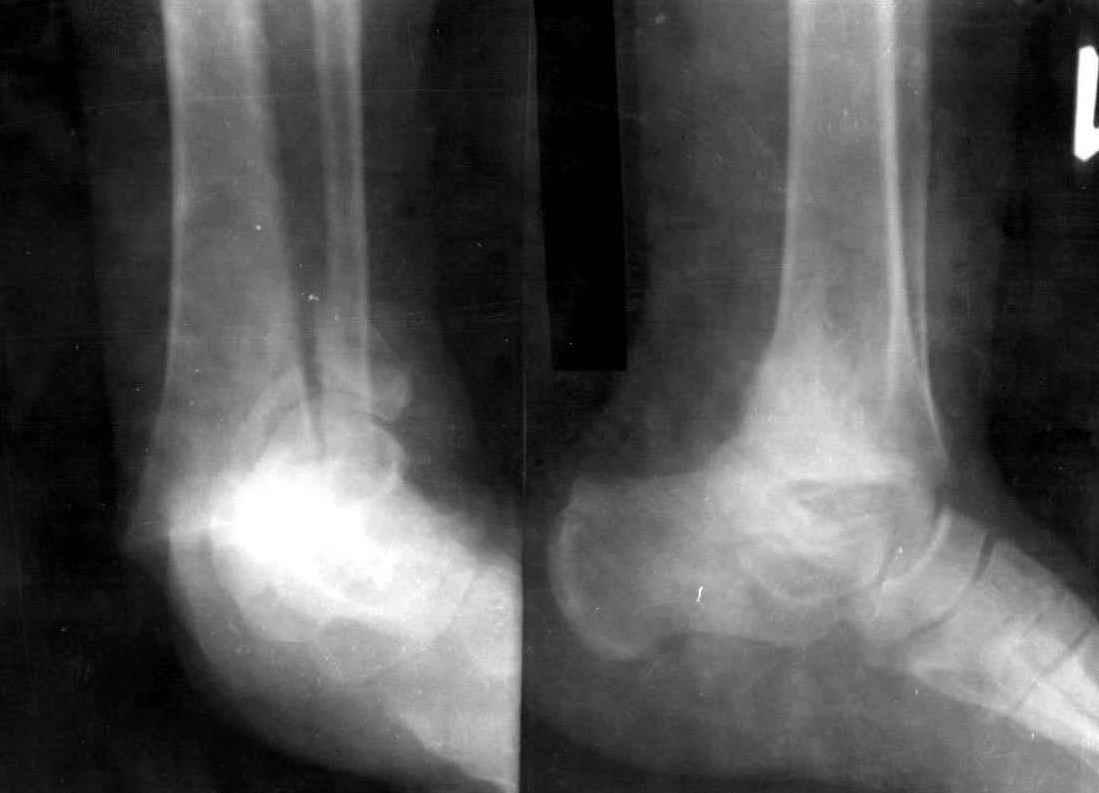

Re: Перелом обеих лодыжек и з/края б/б кости с вывихом стопы

Опарин Сергей 11 Август 2006, 23:36

Рекомендую наложить циркулярный гипс, спицы оставить в окошке. Через 6 -7 недель спицы можно убрать и лечить в гипсе до 8-10 недель.ДОА конечно будет.

Уважаемый С.А. Мелашенко!Если принимать во внимание только тип повреждения (нестабильное), то конечно показана фиксация костей, образующих голеностопный сустав, одним из способов. Но в принятии решения нельза не учитывать такие факторы как: наличие сопутствующих заболеваний, предоперационную мобильность пациентки, массу тела, выраженность остеопороза, желания пациентки (при том, что вы добились приличного стояния отломков)...

Гипсовая иммобилизация, по технологии предпринятого Вами способа лечения, необходима.

Спицы, традиционно, оставляют до трех недель.